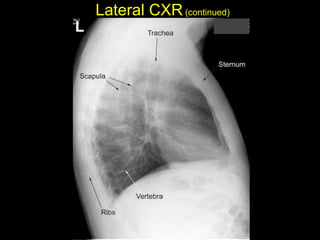

The document discusses the anatomy of the chest x-ray and CT scan by describing the lobes of the lungs and their locations. It also mentions the heart, mediastinum, hilum, and ribs. Several axial, coronal, and sagittal CT images are included with labels pointing out structures like the trachea, bronchi, lobes of the lungs, and fissures. In summary, the document provides an overview of lung and chest anatomy as seen on x-rays and CT scans through text descriptions and labeled medical images.